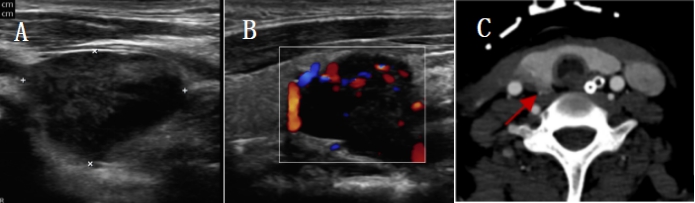

1.3.2 影像学检查2021-04-14彩色多普勒超声:右侧甲状腺下极下方低回声,大小2.3 cm×1.5 cm,边界清,甲状旁腺来源首先考虑(图 1A, B);双肾B超提示:双肾肿大伴肾病表现。2021-04-17颈部CT:右侧甲状腺后方结节(图 1C)。心脏超声:主瓣瓣环及二尖瓣瓣环及二尖瓣腱索上多发钙化,左室壁偏厚,肺动脉压增高。肺部CT:两肺炎症病变,两侧少量胸腔积液(图 2A)。

| A、B:多普勒超声示右侧甲状腺下极下方2.3 cm× 1.5 cm低回声;C:颈部CT示右侧甲状腺后方结节(箭头所指部分) 图 1 甲状旁腺术前影像学定位检查 |